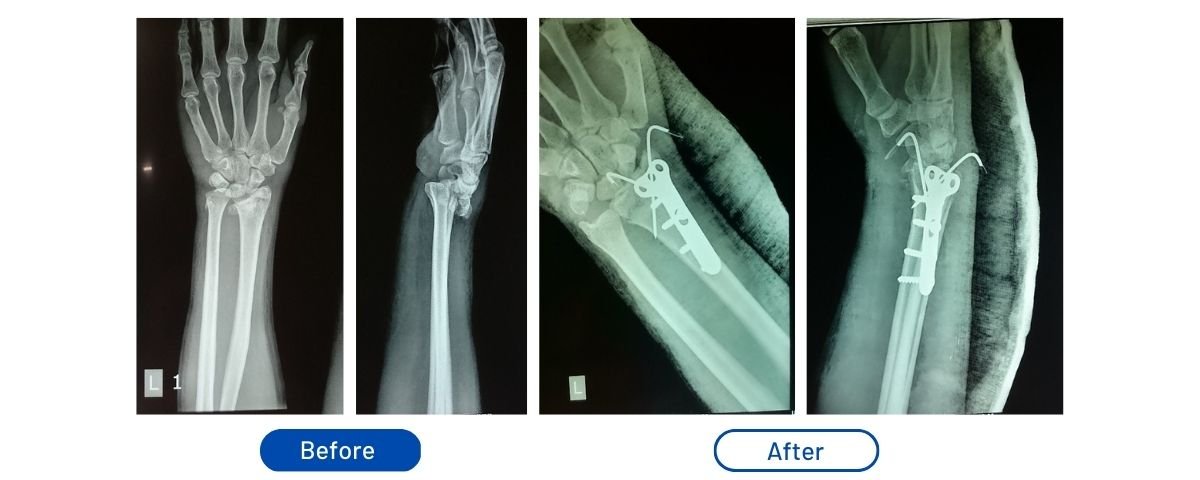

Dorsal Barton's Fracture